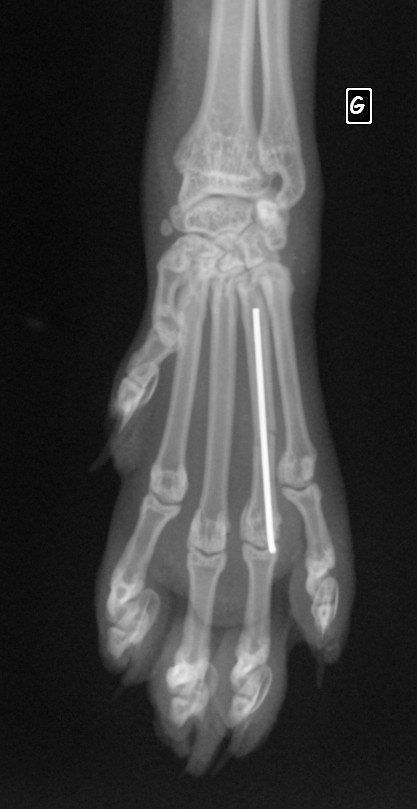

Il a eu le bon réflexe de la déposer chez le vétérinaire du quartier qui a constaté que la petite avait sa patte avant gauche déformée. Il s’est avéré, en grandissant, qu’elle ne se sert pas de sa patte.

Nous l’avons emmené en consultation au CHVA de Beaulieu à Nantes pour avoir l'avis d'un spécialiste. Hélas, il faudra l’amputer car Uanna n’a aucune sensibilité à cette patte. Elle est handicapée et cela devient un fardeau pour elle car Uanna a du mal à se déplacer. Elle s’est blessée plusieurs fois, cela devient urgent pour elle

Coût de l’opération : 1064,20€ (devis en photo)